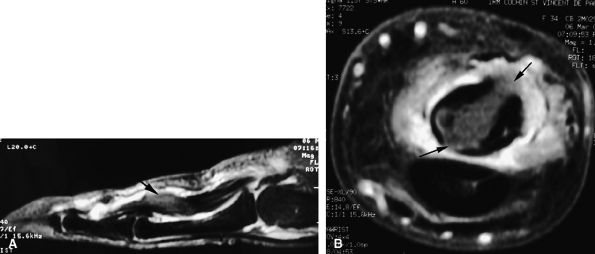

FIGURE 11.47 ● Jersey finger. (A) Sagittal T2-weighted image. (B) Coronal post-contrast T1-weighted images. (C) Axial T1-weighted image. Distal avulsion of the FDP tendon is shown with the proximal end (white arrows) at the metacarpophalangeal joint (type I). The tendon is wavy in the palm (arrowheads). The empty digital canal (in C) may mimic a remnant tendon, but the FDS tendon (asterisk) is alone in the canal.

|